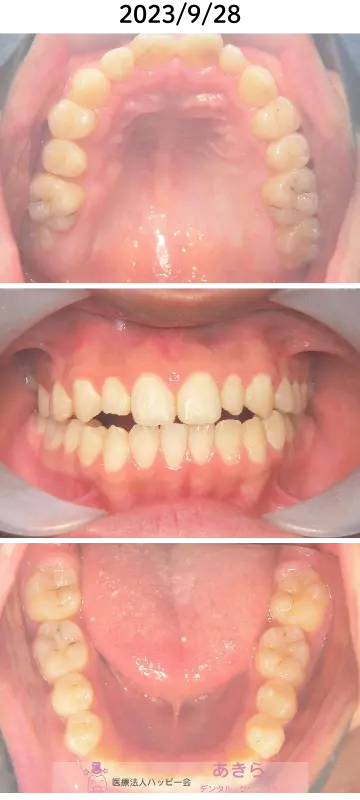

2023年9月28日 口腔内写真(経過)

- 2021年6月より「SHA=SH装置」SH療法スタート

- 歯列が直立してくることにより、早期接触が起こりますので、随時必要枠での咬合調整が必要になります。

- SHA修理 上顎2回 下顎1回